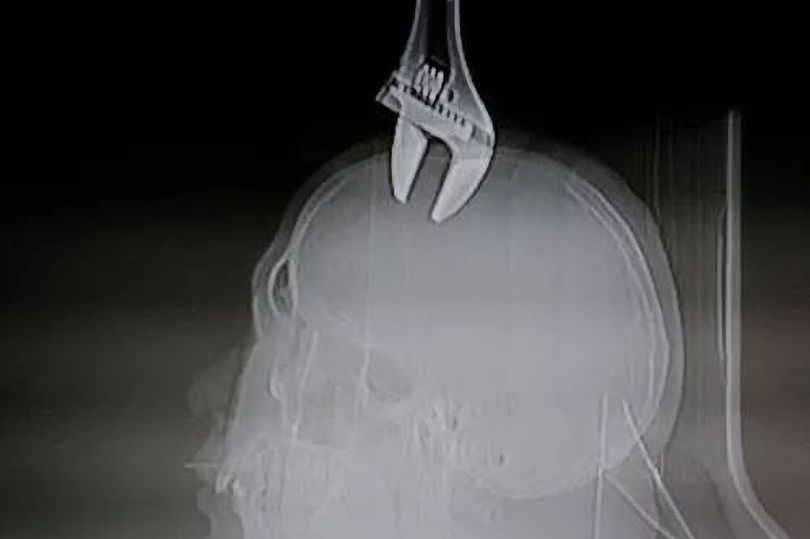

Ảnh chụp X-quang cho thấy chiếc cờ lê găm sâu vào đầu bệnh nhân.

Ảnh chụp X-quang cho thấy cờ lê găm sâu vào hộp sọ người đàn ông theo góc đúng 90 độ. Nạn nhân được xác định khoảng 50 tuổi, là doanh nhân đang có chuyến công tác ở thành phố.